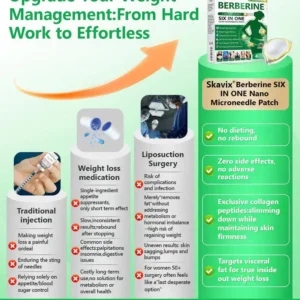

What if one simple patch a day could help you feel more balanced, refreshed, and comfortable in your everyday life — without complicated routines? That’s exactly what Skavix® Berberine 6-in-1 Nano Microneedle Patch is designed for. With advanced nano microneedle technology and carefully selected ingredients, the patch works gently throughout the day to support daily balance and overall wellbeing. Many people notice that over time they feel more refreshed, more comfortable in their body, and more confident in their daily life. Sometimes a small daily habit can make a meaningful difference.

Appetite Suppressant Advantage:

𝑩𝒆𝒓𝑏𝘦𝘳𝑖𝗇𝒆,𝑩𝒆𝒓𝑏𝘦𝘳𝑖𝗇𝒆 HCI and NAD+work continuously on thecentral nervous system. They enhance satiety signals, disrupt hunger cues, and reshapelong-term eating habits. As a result, users naturally reduce food intake,lower daily calorie consumption, and build asolid foundation for weight loss.

Metabolic Synergy:

At the cellular level, 𝑩𝒆𝒓𝑏𝘦𝘳𝑖𝗇𝒆 and moringaactivate key metabolic pathwaysin fat cells, liver cells, and skeletal muscle cells. They promote lipolysis by breaking down triglycerides into free fatty acids and efficiently transporting them to mitochondria for oxidation and energy production. They also boost basal metabolic rate, accelerating peripheral energy expenditure. This dual-action mechanism helps the body burn excess fat, leading to weight loss, while thesynergistic metabolism ensures stable results and prevents rebound.

Post-Weight Loss Skin Care:

After rapid weight loss, skin often becomes loose, saggy, and less elastic.

Skavix® has specially addedCollagen Peptidesand collagen-boosting factors to the formula. These key ingredients stimulate collagen and elastin synthesis, helping the skin regain firmness and thickness. They also smooth fine lines, reduce sagging, and restore a youthful, healthy glow. This ensures you not only lose weight successfully but also maintain a toned, youthful physique—avoiding the problem of “looking older after slimming down.”Weight loss and rejuvenation are achieved simultaneously.